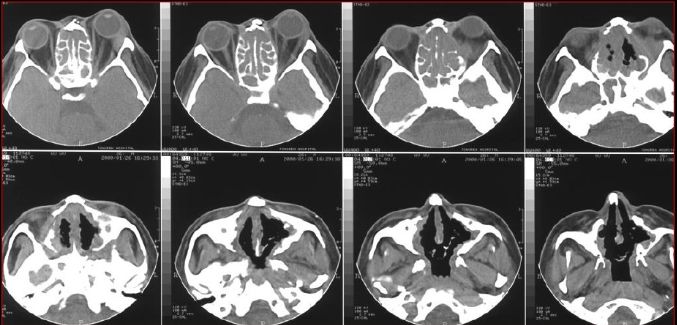

蝶窦炎—眶尖综合症

鼻窦炎—眶尖综合症